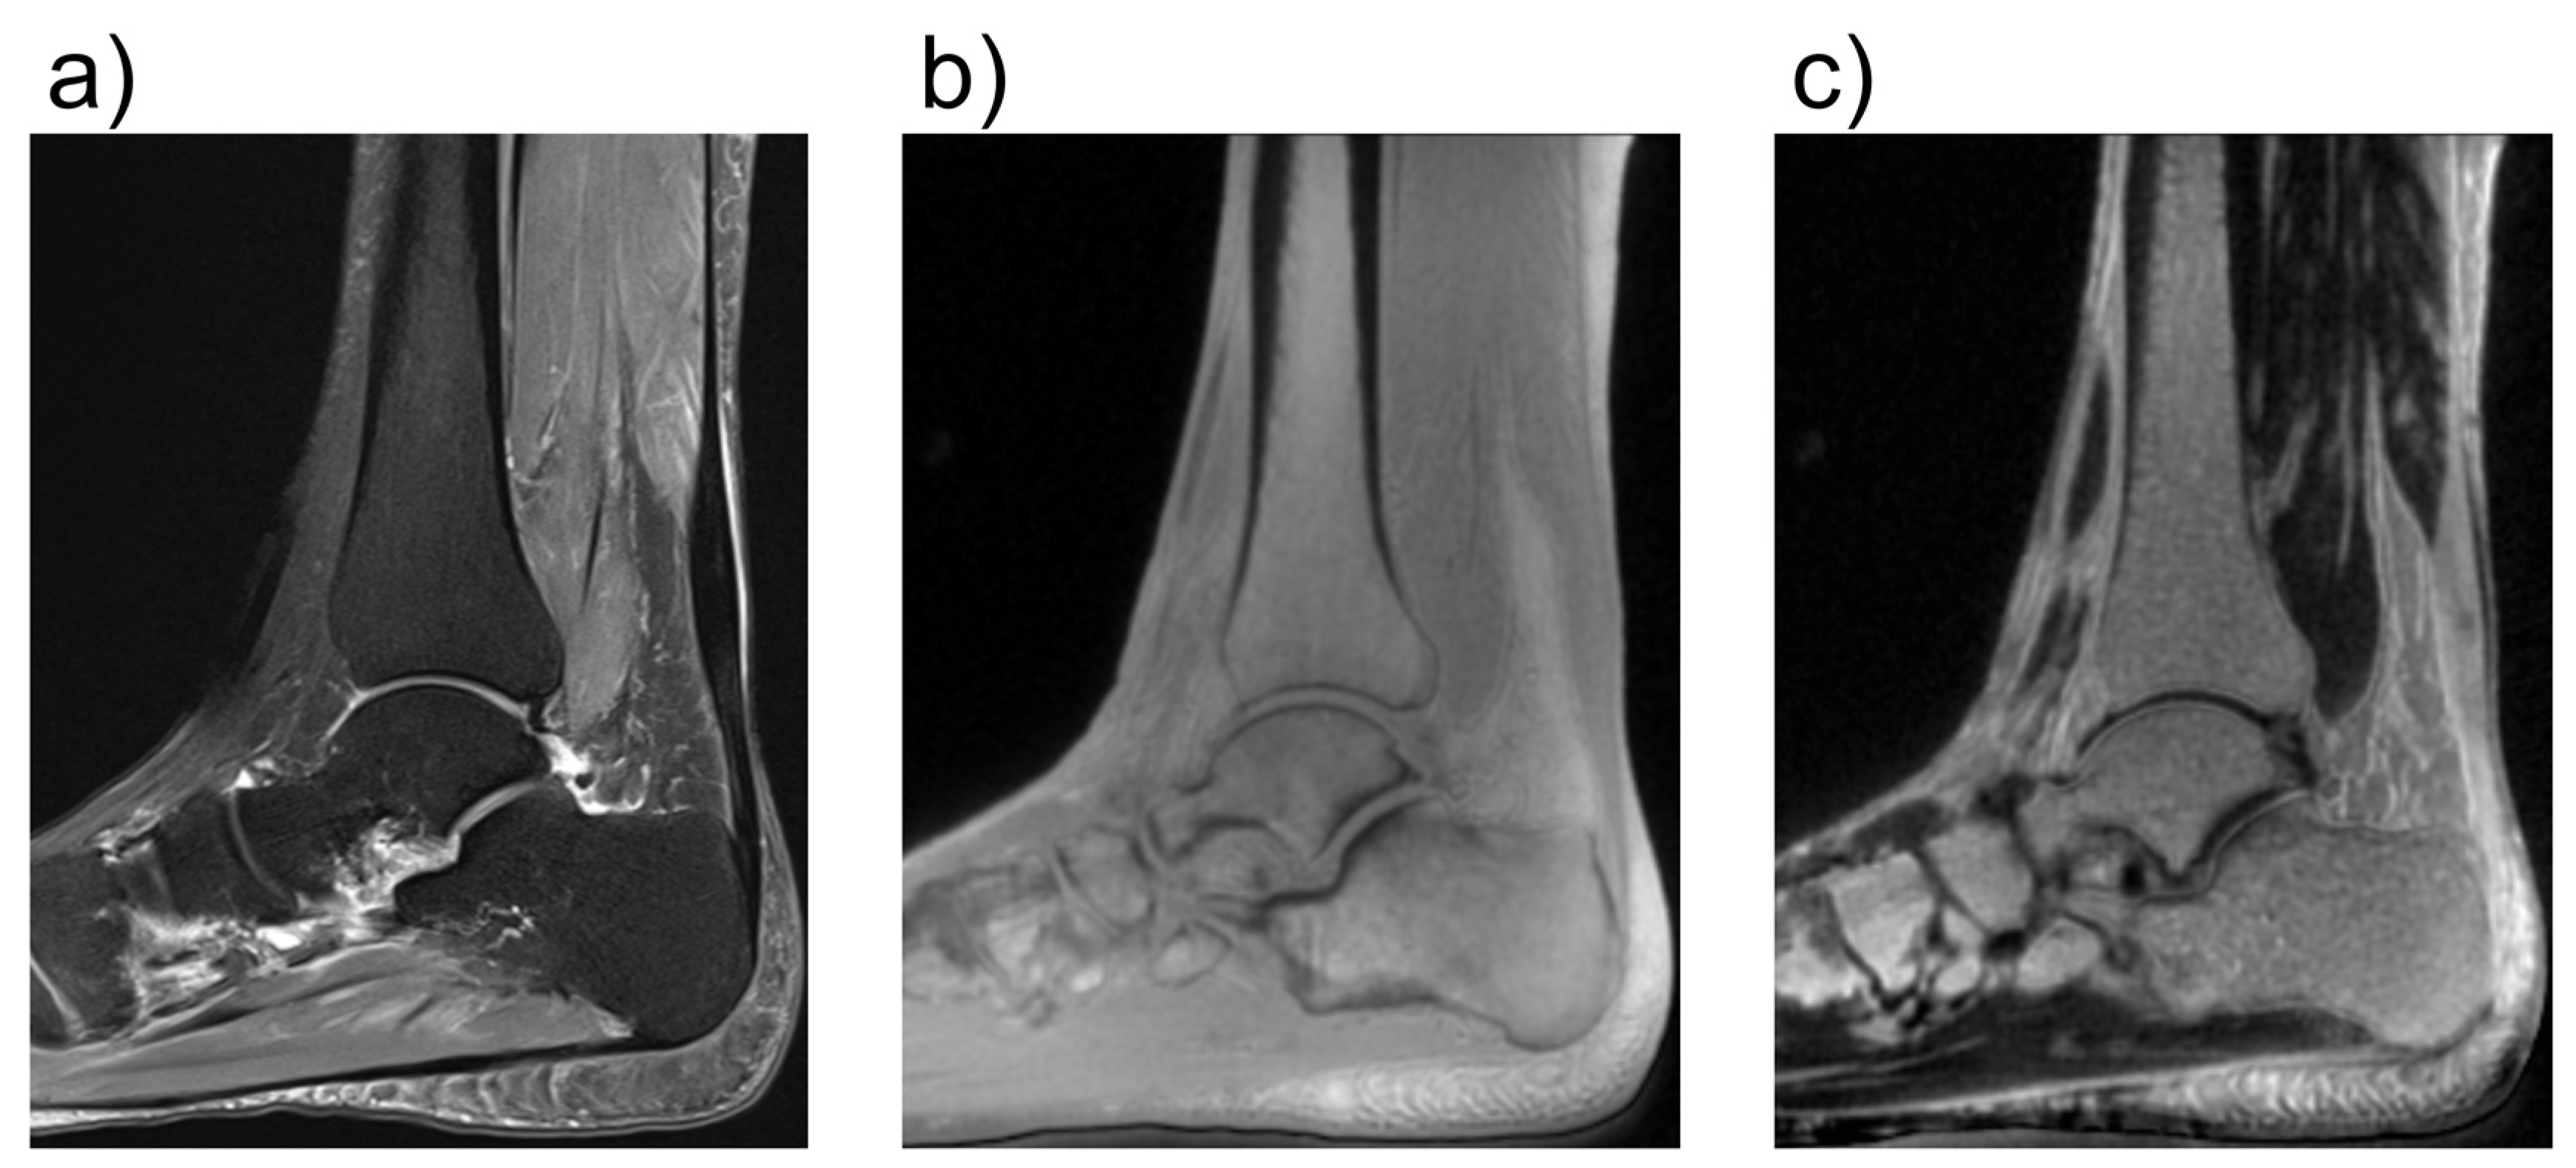

- Albano, D.; Martinelli, N.; Bianchi, A.; Giacalone, A.; Sconfienza, L.M. Evaluation of reproducibility of the MOCART score in patients with osteochondral lesions of the talus repaired using the autologous matrix-induced chondrogenesis technique. Radiol. Med. 2017, 122, 909–917. [Google Scholar] [CrossRef] [PubMed]

- Albano, D.; Martinelli, N.; Bianchi, A.; Messina, C.; Malerba, F.; Sconfienza, L.M. Clinical and imaging outcome of osteochondral lesions of the talus treated using autologous matrix-induced chondrogenesis technique with a biomimetic scaffold. BMC Musculoskelet. Disord. 2017, 18, 306. [Google Scholar] [CrossRef] [PubMed]